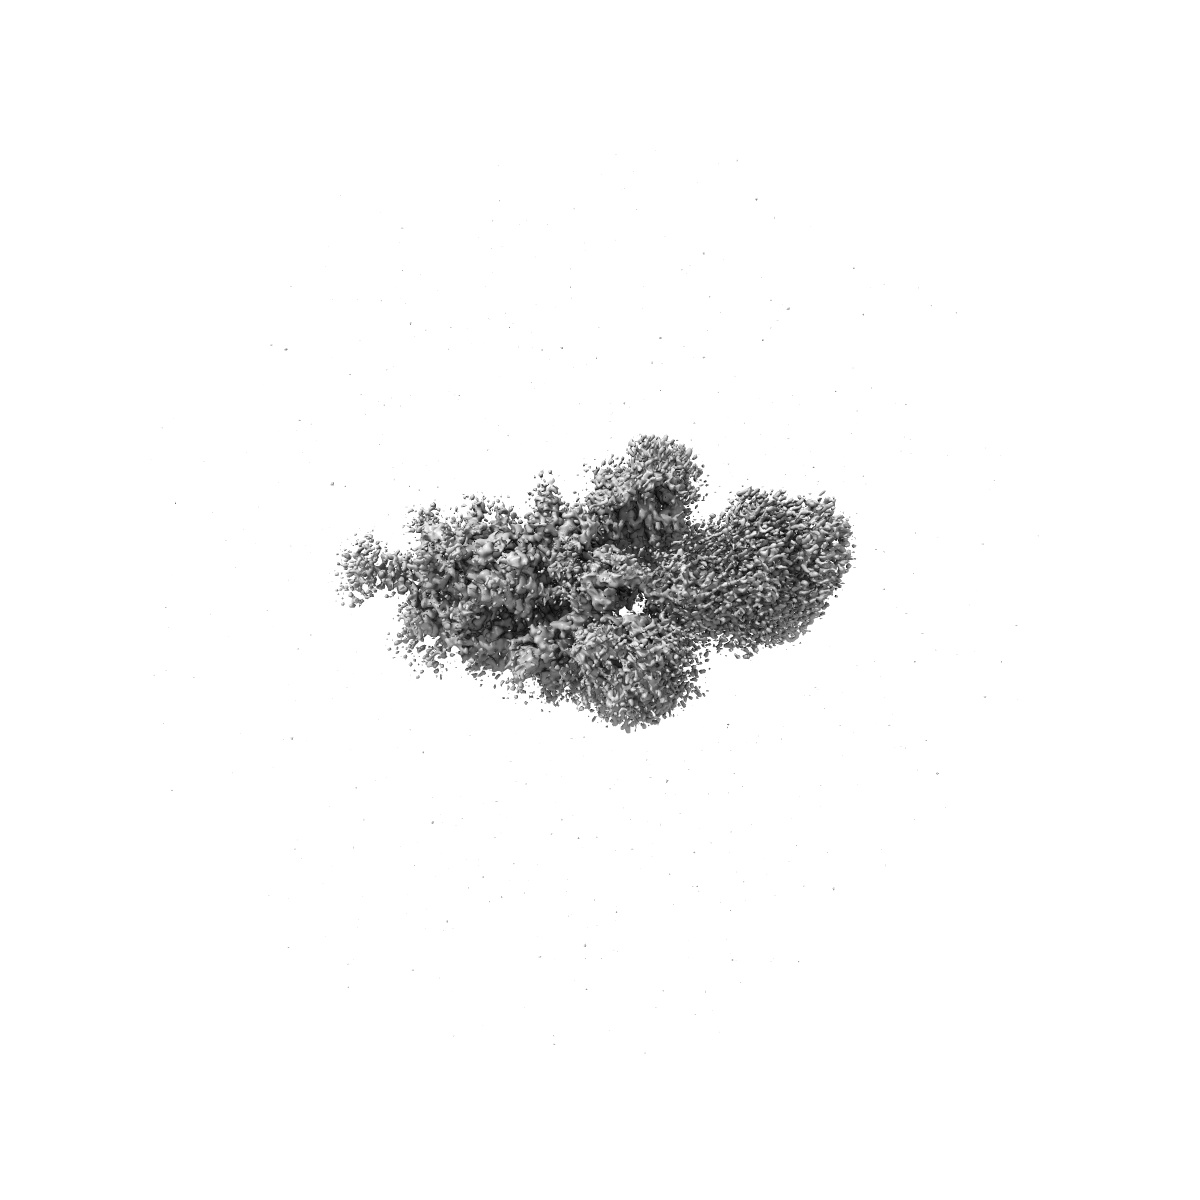

Cryo-EM structure of mink variant Y453F trimeric spike protein bound to two mink ACE2 receptors

Single-particle3.36 Å

Sample: Cryo-EM structure of mink variant Y453F trimeric spike protein bound to two mink ACE2 receptors